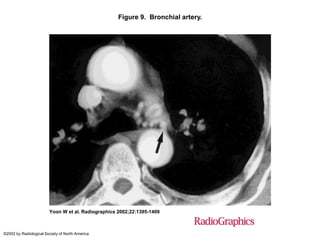

Figure 9. Bronchial artery.

Yoon W et al. Radiographics 2002;22:1395-1409

©2002 by Radiological Society of North America

Figure 9. Bronchialartery. Yoon W et al. Radiographics 2002;22:1395-1409 ©2002 by Radiological Society of North America

• #29 Figure 9.  Bronchial artery. Contrast-enhanced CT scan shows a pathologic left bronchial artery (arrow) that originates from the anterior wall of the descending thoracic aorta.